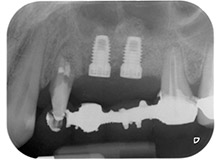

Postoperative radiograph

Fig. 16: Postoperative radiograph showing the implants in place, with bone substitute material from the internal sinus lift around the apices. There is some material from the GTR procedure visible around the roots of tooth 24.

Finally, after periosteal incision, the site was passively sutured with a coronally advanced flap, using 5-0 absorbable suture material (Fig. 15). The postoperative radiograph showed both implants in their correct vertical position (Fig. 16).